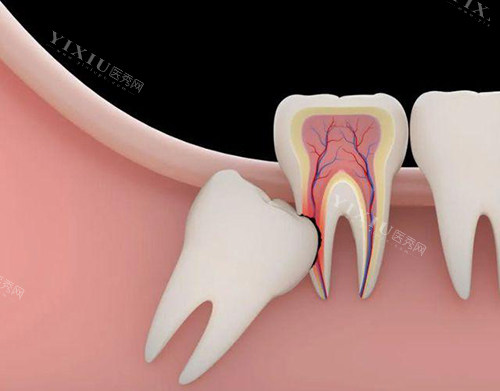

拔牙那天,我早早地就到了医院,心里像有个小兔子在乱跳。医生先让我拍了牙片,检查智齿的生长情况。我看着牙片上那颗歪歪扭扭的智齿,心里就更没底了。医生看完牙片后,告诉我这颗智齿位置不太好,拔起来可能会有点复杂,但不用担心,他们会尽量减轻我的痛苦。听到这话,我紧张得手心都冒汗了。